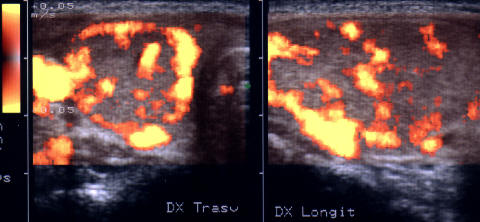

Aceeasi pacienta. La doppler color si powercolordoppler – crestere marcata a vascularizatiei glandei.